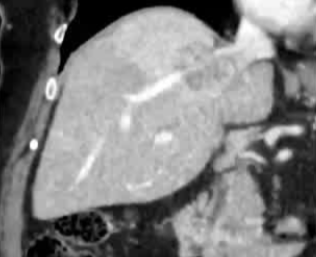

· 单中心、样本量小; 83 岁的女性,体重超标 40 毫米单发 ICC(S7-S8) 中肝静脉和右肝静脉浸润性,活检:非酒精性脂肪性肝炎(慢性肝病),马斯氏(MaS)病(30%)

考虑采用“三步策略 TARE→ PVE → Surgery”方案 剂量活性:1.56 和 3.16 GBq